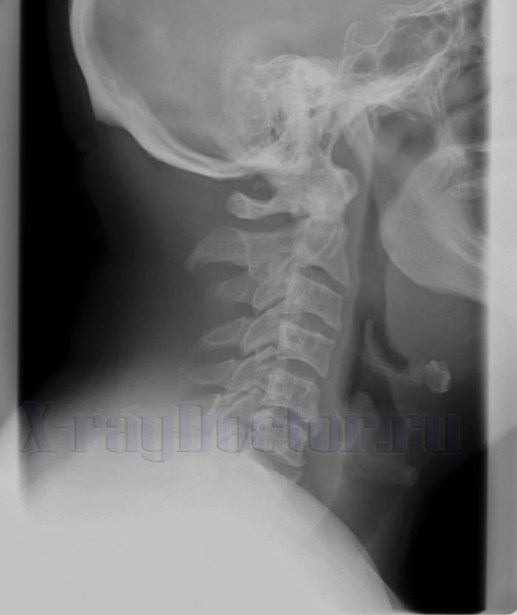

Вышеперечисленные структуры хорошо видны на боковой рентгенограмме.

Рентген-снимок показывает разные виды смещений органа в сочетании с изменениями надгортанника, корня языка и подъязычной кости.

Хрящевые структуры на снимке виды при их обызвествлении. Такие изменения наблюдаются обычно у людей в 70-80 лет.

Вначале обызвествляется щитовидный хрящ, затем перстневидный и черпаловидные связки.

Рентгенологическое обследование позволяет изучить морфологическое состояние органа, выявить сужения и деформации на пути следования воздушного столба. Рентгеновское исследование нередко позволяет выявить опухолевые образования и инородные тела.